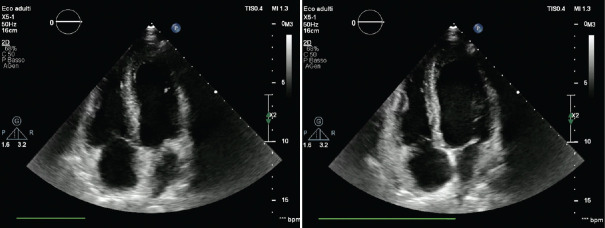

Abstract Image